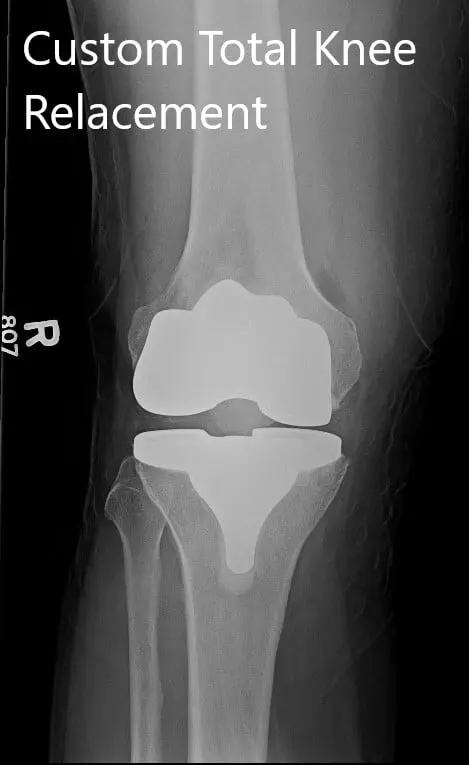

Postoperative X-ray showing AP and lateral images of the right knee

IMPLANTS USED: Custom femur with a Custom tibia with 10-mm polyethylene insert with a 32-mm x 6-mm patella.